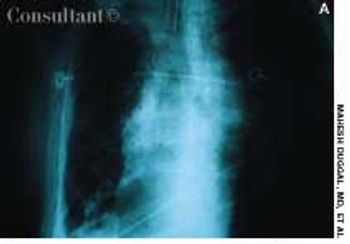

A 72-year-old nursing home resident was hospitalized with fever, chills, and rigors of 2 days' duration. The nursing home staff reported the patient had dysphagia after a recent stroke.